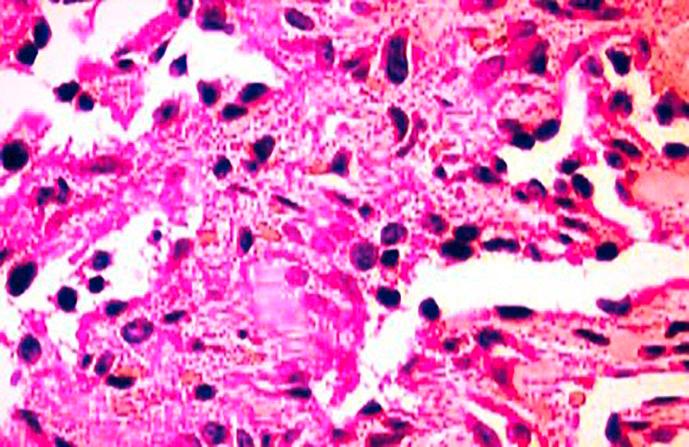

In this case report, we have reported a rare case of RH, a locally aggressive, vascular tumor of malignant potential presenting at an unusual site. The most observed locations of this soft tissue tumor are skin and subcutaneous tissues of extremities; however, this case of RH was observed in an unusual site called pleura, which is a rare occurrence related to this tumor. The presence of cell surface markers like CD31 and ERG of vascular and endothelial origin and the presence of hobnail appearance of endothelial channels on the biopsy profile supported the vascular origin of the tumor; the clinical features and imaging studies further confirmed the diagnosis of RH.

在本病例报告中,我们报告了一例罕见的RH病例,这是一种具有局部侵袭性、有恶性潜能的血管肿瘤,出现在一个不寻常的部位。这种软组织肿瘤最常出现的部位是四肢的皮肤和皮下组织;然而,该例RH出现在一个名为胸膜的不寻常部位,这与该肿瘤相关的情况罕见。活检结果中血管和内皮来源的细胞表面标志物如CD31和ERG的存在以及内皮通道的鞋钉样外观支持了肿瘤的血管起源;临床特征和影像学研究进一步证实了RH的诊断。